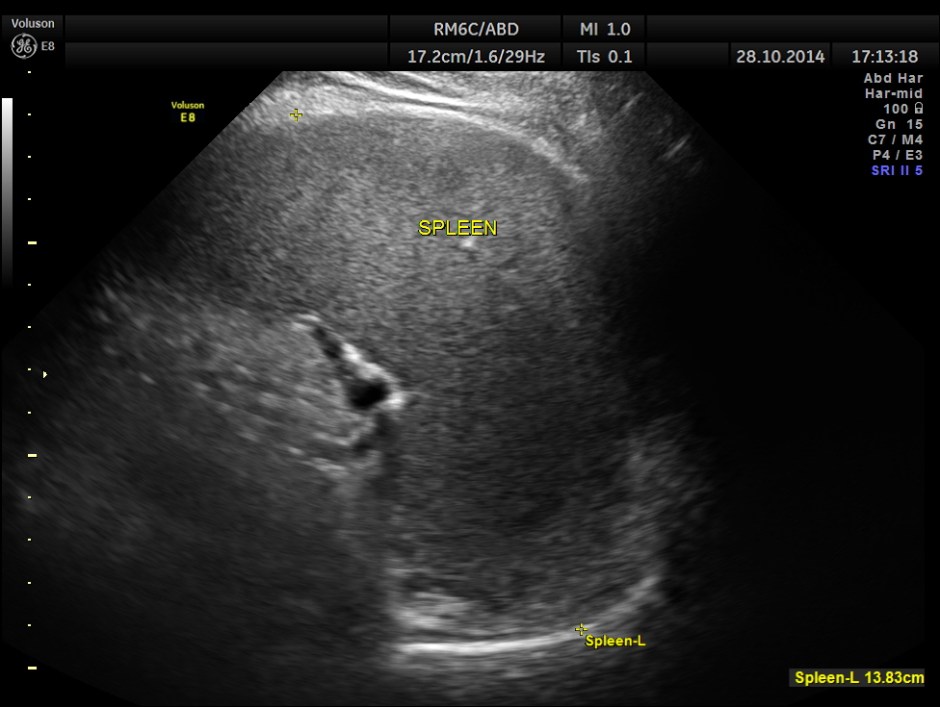

Mild splenomegaly with mildly dilated splenic vein is seen.